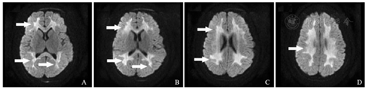

患儿,女,5岁,因呕吐、腹泻、反复惊厥致昏迷入院,诊断为脓毒症相关性脑病。图A~D为患儿入院当日MRI,扩散加权成像序列显示脑室周围白质对称性高信号,损伤区域包括半卵圆体和冠状辐射(白色箭头)。